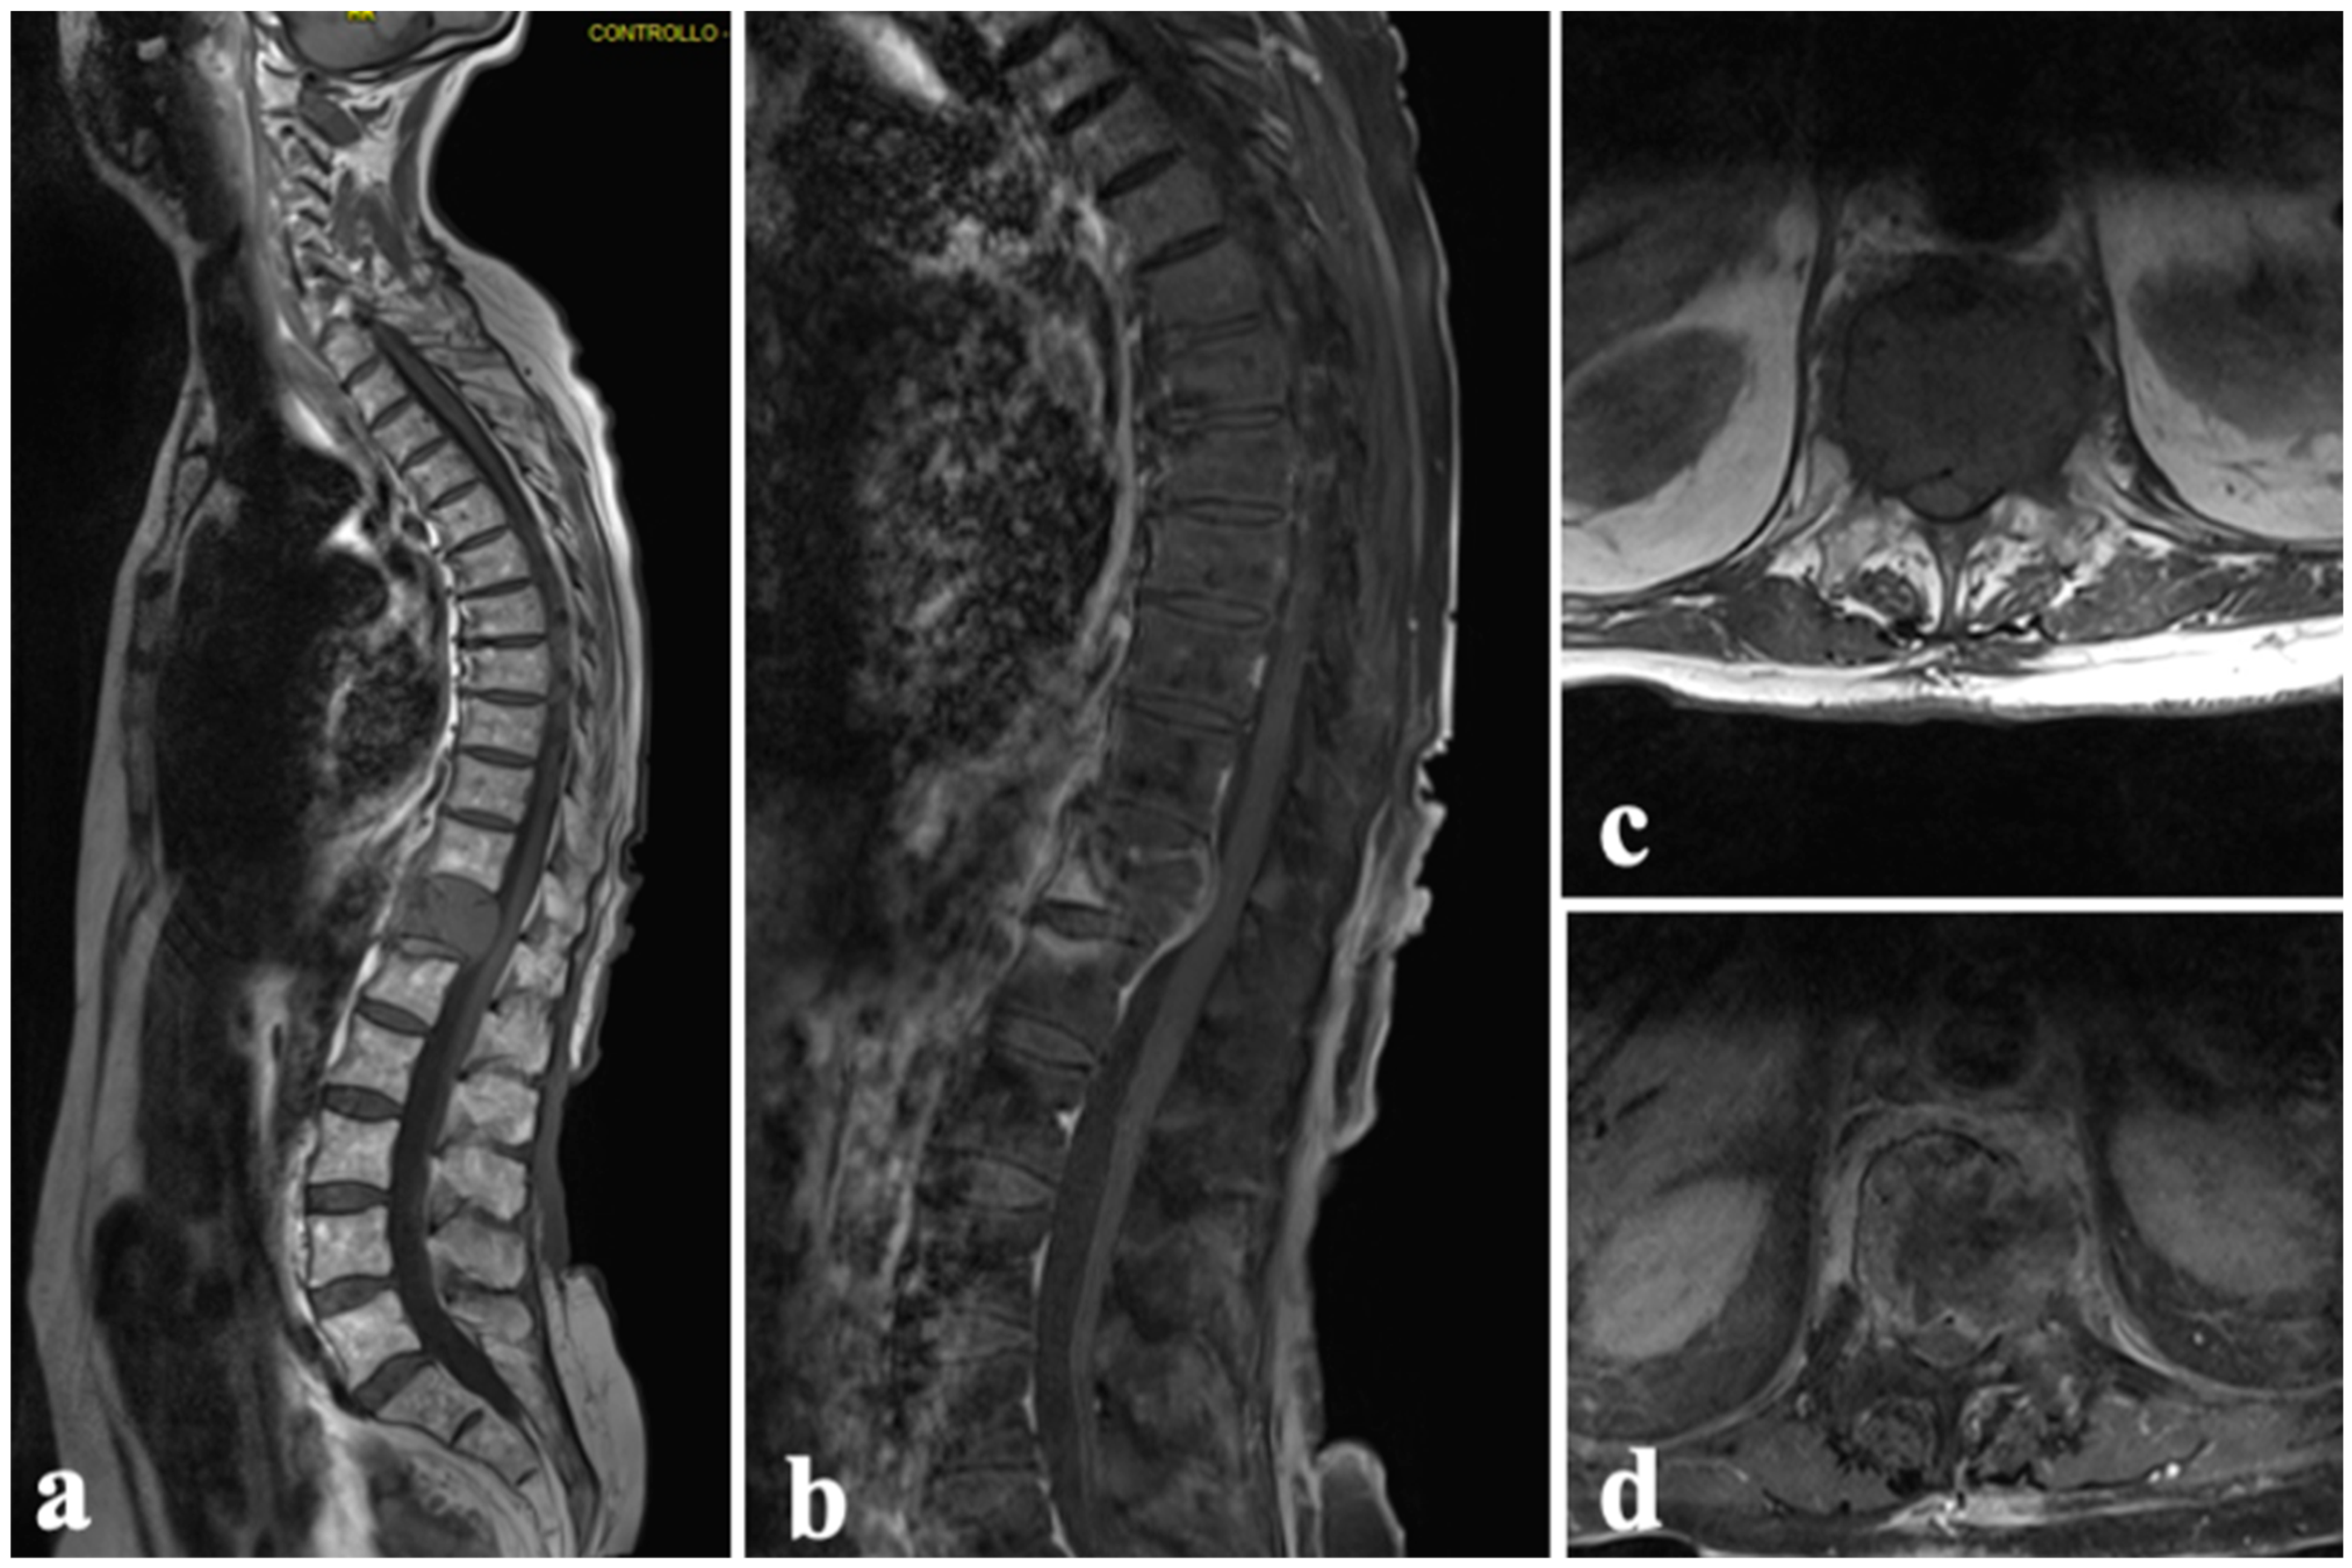

A 73-year-old male patient with no history of tumor presented with swelling in the left ankle for about a year, with a notable increase in size in the last 3 months. An MRI of the left ankle showed a soft-tissue lesion in the distal third of the leg with no erosion of the bony cortex. A needle biopsy with histological evaluation was performed, resulting in the diagnosis of leiomyosarcoma G3 with areas of necrosis (30%) desmin +, caldesmon +, and smooth muscle actin +. A below-knee amputation was performed with histological confirmation of both tibial and fibular bone infiltration and wide margins.

During follow-up, a CT scan of the chest and abdomen for restaging showed multiple metastases in the pectoral region, left gluteal region, left ischiopubic branch, and the vertebral soma of D11, with the involvement of the posterior wall and partial spinal cord compression (Figure 8a,b). Given the effective pain control and the absence of neurological symptoms, conservative treatment with a spinal brace was proposed for the thoracic metastatic lesion, along with chemotherapy. During the first month, the patient experienced clinical worsening (ASIA scale D), reporting an increase in pain to VAS and a decline in oncological indices (Karnofsky 50%, Tokuashi 9, and Tomita 6). Therefore, surgical treatment was considered. Surgery consisted of spinal cord decompression in D11, spinal stabilization from D10 to L1, and ECT with bleomycin administered at the D11 vertebra (Figure 8c–f), with immediate pain relief (VAS 2) and neurologic restoration (ASIA scale E). The patient was alive with disease at the 6-month follow-up, with stable disease observed in the vertebral site.

Figure 8.

Case 3. A 73-year-old man with T11 metastasis from leiomyosarcoma grade 3: (a,b) axial CT scan shows the lytic lesion with spinal cord compression; (c) positioning of the patient; (d) insertion of the electrodes; (e) connection of the electrodes with the pulse generator; (f) definitive instrumentation and laminectomy.